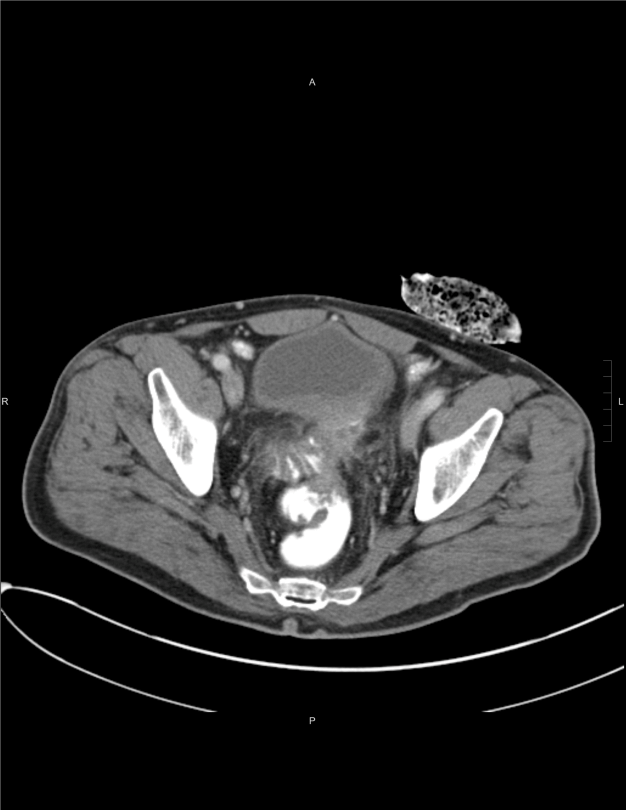

Image from a CT scan.A 60-year-old male underwent robotic-assisted colorectal surgery at UPMC Montefiore in April 2025.

Back in July 2024, the Somerset County resident presented with fecaluria (he was passing stool in his urine). He saw his local doctor and underwent a CT scan, cystoscopy, colonoscopy, and a visit with a general surgeon before receiving his diagnosis of a colovesical fistula, which is an abnormal connection between the colon and the bladder.

“That was even more evidence that something wasn’t quite right,” adds Dr. Cunningham, who scanned him and found radiographic evidence of a connection between the patient’s rectal stump and his bladder.